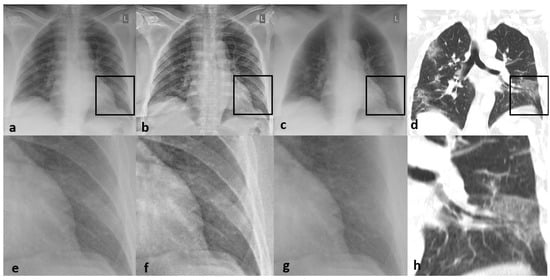

3.3. Imaging Findings